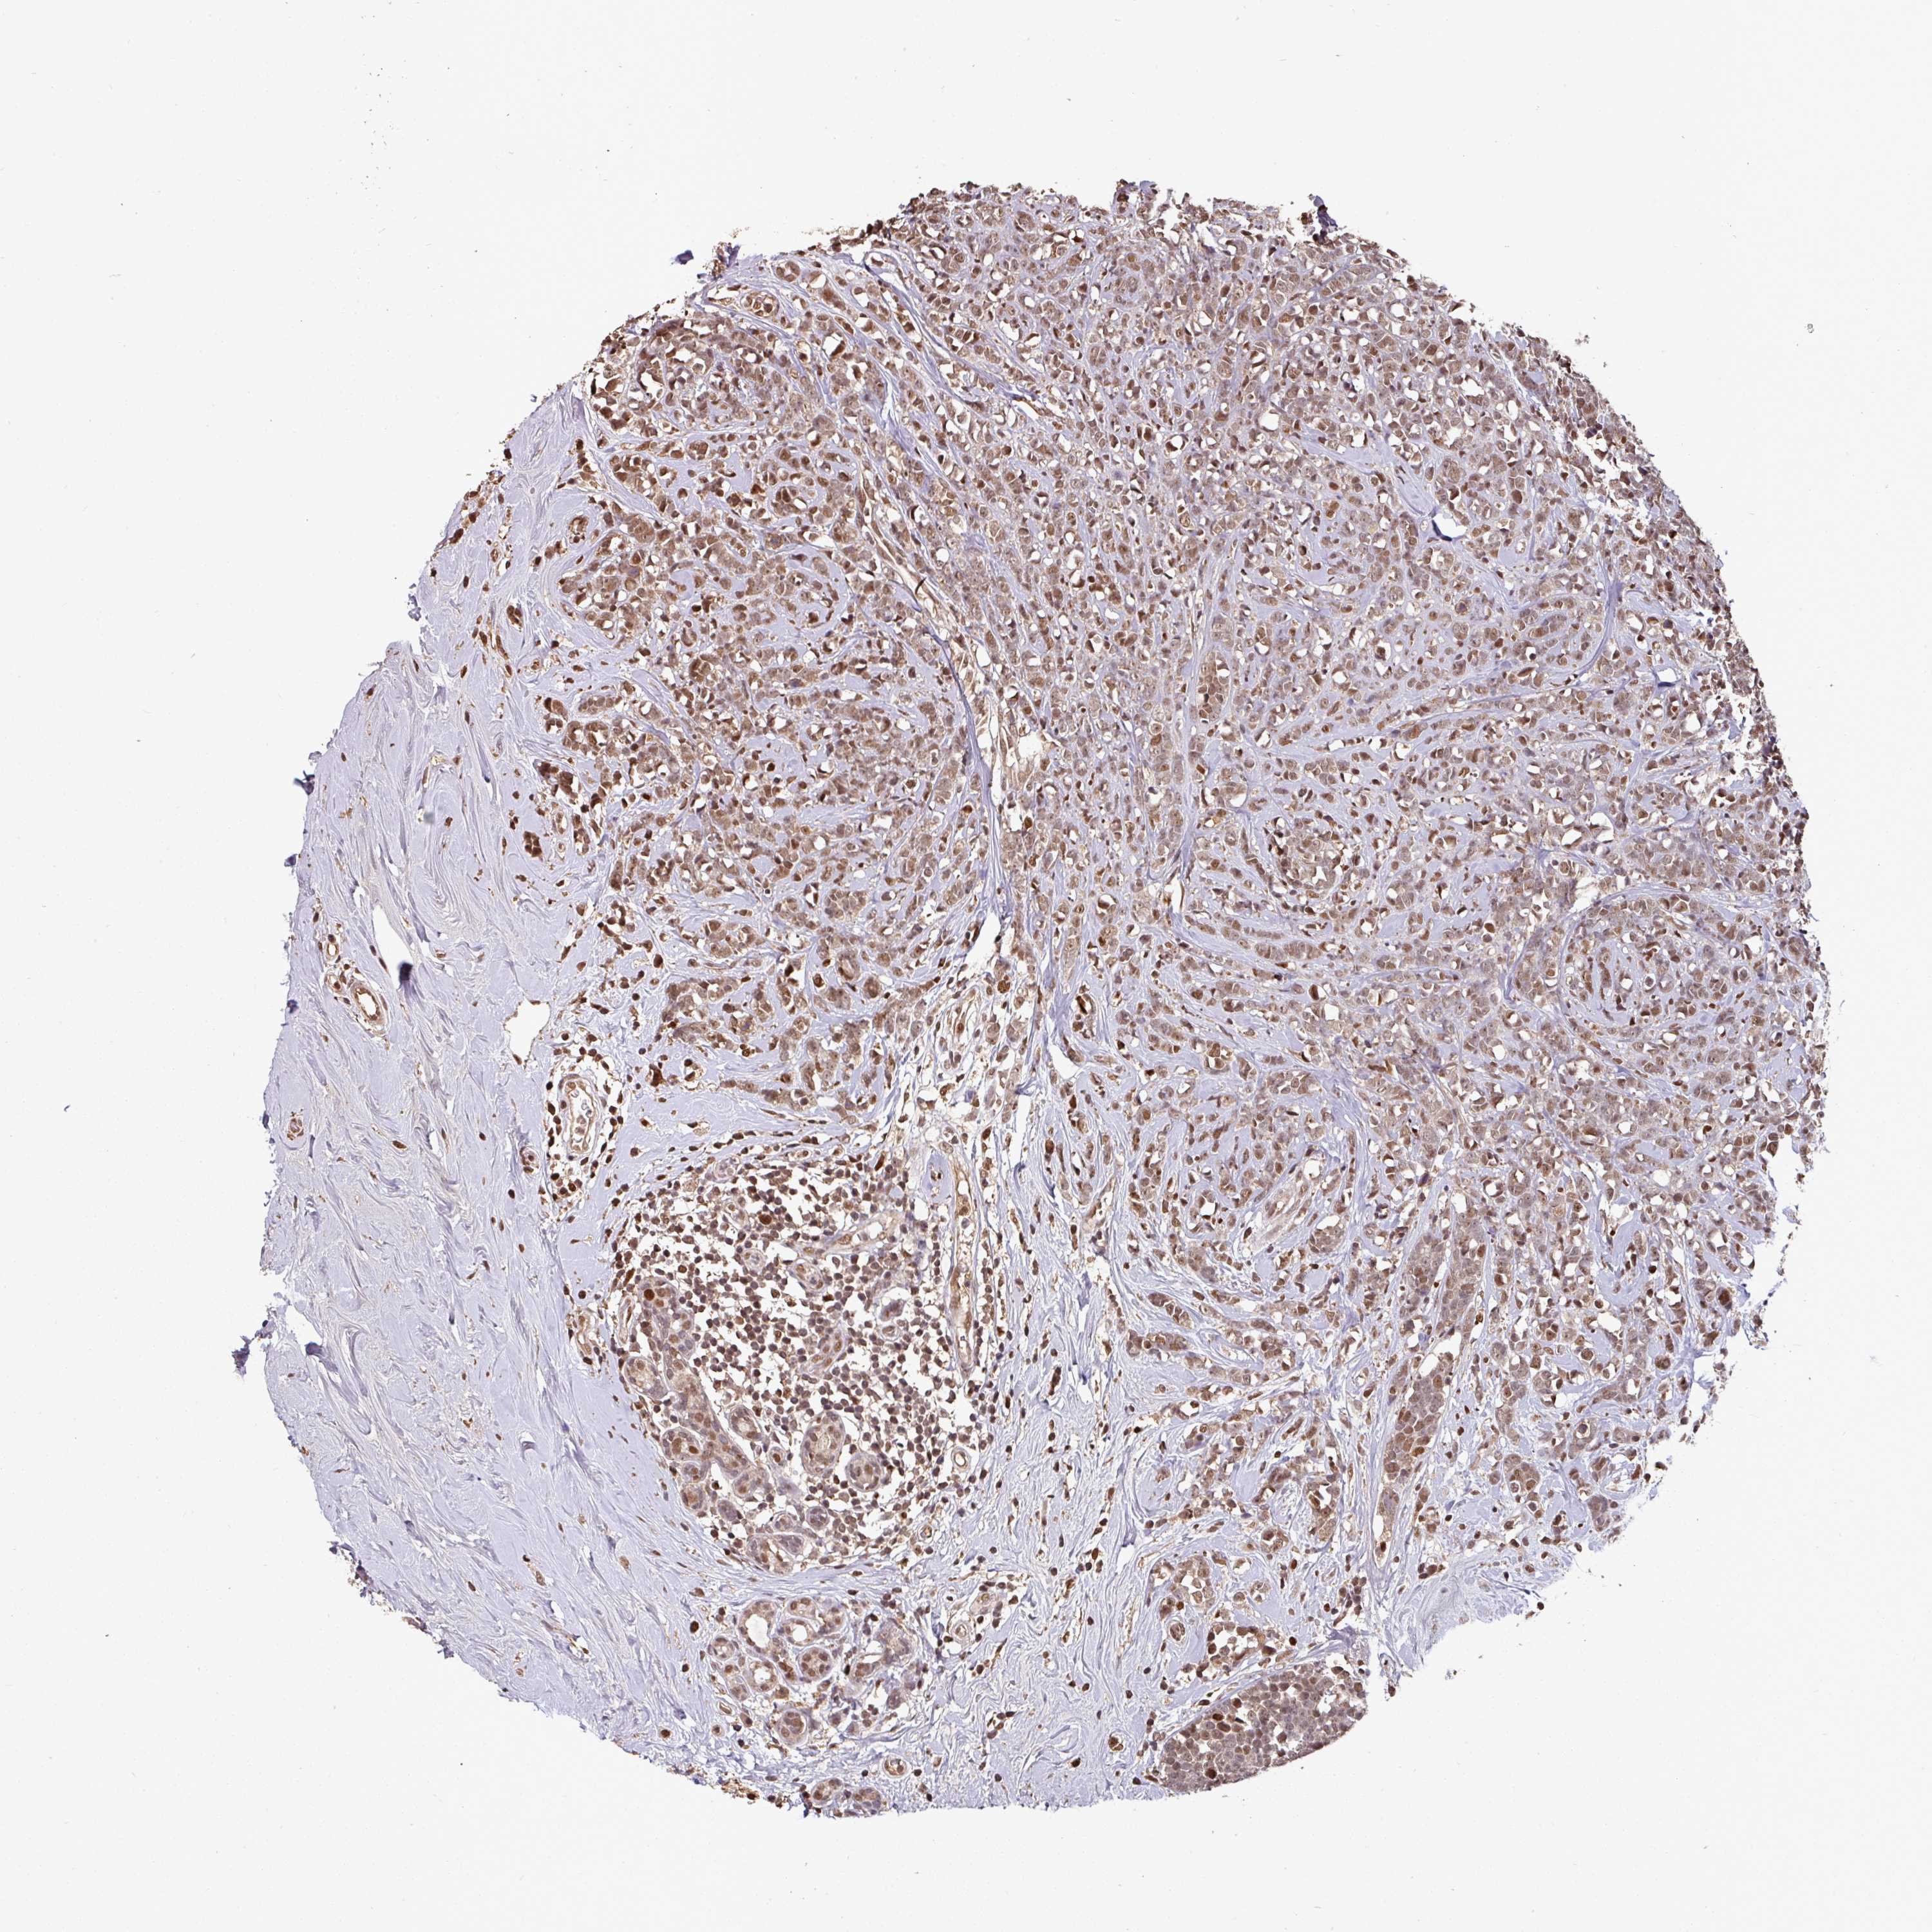

BRCA TCGA BRCA VALIDATION PROTEIN EXPRESSION

ANTIBODIES

AND

VALIDATION